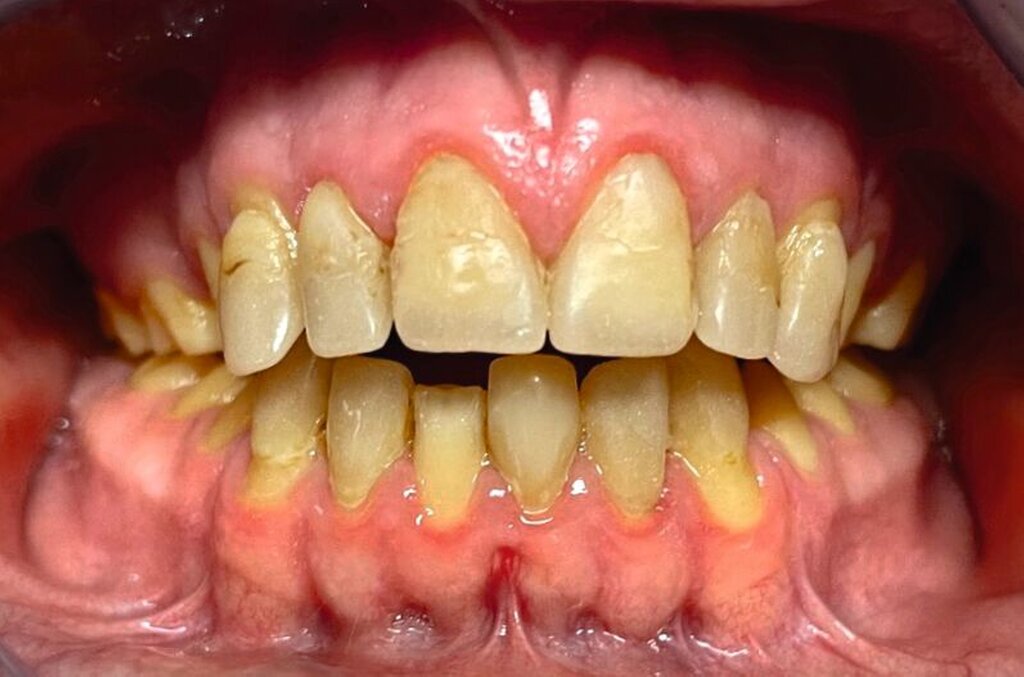

Klinisch zeigten sich ein nicht-kariöses Wechselgebiss mit generalisierter Schmelzhypoplasie an allen Zähnen sowie eine insuffiziente Mundhygiene. Zusätzlich bestanden eine fehlende Mittellinienübereinstimmung, ein Overbite von minus vier Millimetern und ein Overjet von sechs Millimetern (Abbildung 5), die sich phonetisch in einem interdentalen Sigmatismus äußerten. Röntgenologisch waren alle Zähne angelegt, jedoch war der Zahnschmelz stark reduziert oder vollständig fehlend (Abbildung 6).